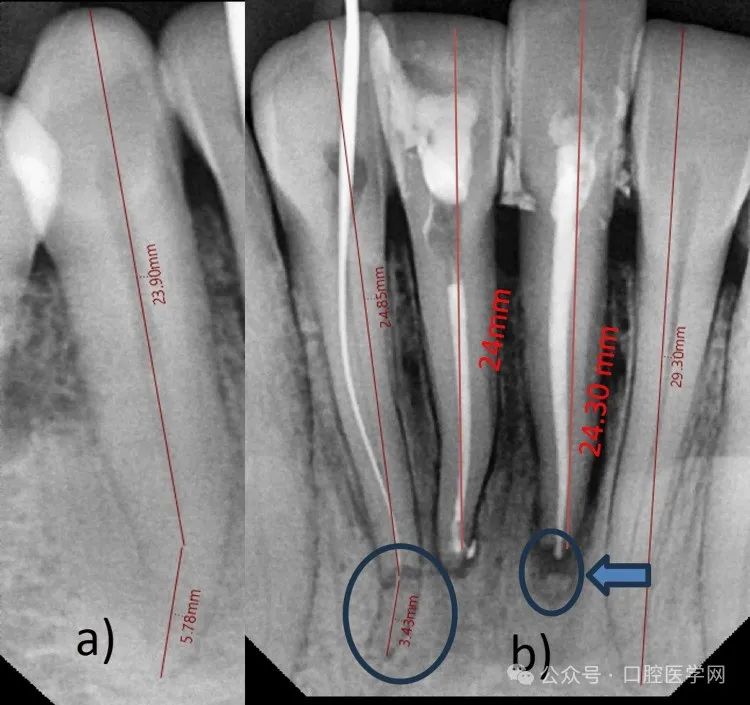

使用Vatech口内传感器拍摄放射片,通过EZ Dent软件(Vatech印度私人有限公司,新德里,印度)阅片(图2)。

a) 右下尖牙长度=30毫米;b) 左下侧切牙29毫米,右下侧切牙28.3毫米,右下侧切牙根尖三分之一水平根折(蓝色圆圈);右下中切牙24毫米,左下中切牙25毫米(冠方断端=24.3毫米,根尖断端0.7毫米),伴根尖三分之一根折(蓝色箭头及圆圈)

影像学分析显示:右下侧切牙(42号牙)根尖三分之一水平根折,根尖三分之一呈远中弯曲,根长超出正常范围(根尖断端3.43毫米,冠方断端24.85毫米)。右下中切牙(41号牙)根尖周损伤(<0.5毫米),总长度24毫米。左下中切牙(31号牙)根尖三分之一小水平根折伴牙周膜增宽,根尖断端0.7毫米,冠方断端24.3毫米,总长度25毫米。左下侧切牙(32号牙)总长度较长(29.3毫米)伴远中扩张。双侧下颌尖牙(43和33号牙)长度约30毫米。